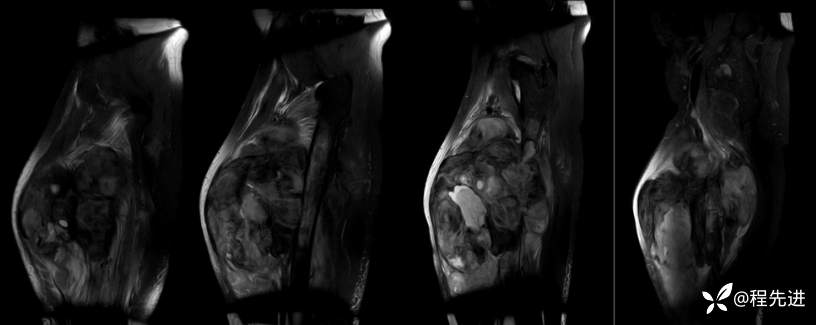

MR

T2矢状位